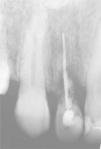

En los hallazgos radiográficos se apreció resorción radicular externa en la zona del cuello del diente y anquilosis (Figura 3).